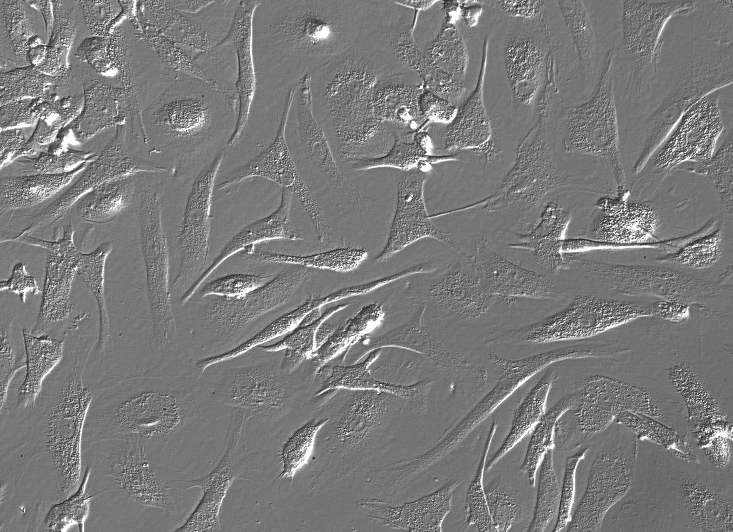

- 细胞形态:

上皮细胞样

生长特性:贴壁细胞

细胞形态:上皮细胞样

生长培养基:DMEM高糖(PM150210)+10% FBS(164210-500)+1% P/S(PB180120)

推荐传代比例:1:3-1:4

推荐换液频率:2-3次/周

背景描述:H4人脑神经胶质瘤细胞建系于1973年;它衍生于一个患神经胶质瘤的37岁病人的脑组织。H4细胞的致瘤特性己经被屏蔽,细胞接种动物一般不产生肿瘤结节。H4细胞具有修复MNNG损伤5型腺病毒的能力。